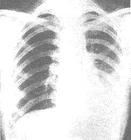

1.詳細詢問異物吸入史,在採集病史時要耐心細緻,必要時應予啟發。2.充分利用X線檢查手段,發現陽性體徵,提高診斷正確率。凡以呼吸系統症狀為主訴就診的患兒,應常規作胸部X線透視及拍攝平片。注意觀察有無縱隔擺動、肺氣腫或肺不張,因這些X線陽性體徵是支氣管異物的間接證據,對於金屬類異物並能得到直接證據。當然,X線檢查正常也不能完全排除異物的存在,對異物位於氣管者更是如此。必要時應及早作支氣管鏡檢查。

4.X線檢查可能有縱隔擺動、肺不張、肺氣腫。異物如為金屬即可確診。